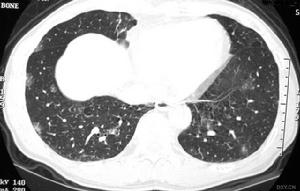

7.胸部X線檢查可呈斑點狀、結節狀或雲絮狀陰影。麴黴球典型的徵象為密度均勻似球狀,其上方有薄壁半月形透亮區,麴黴球可隨體位變動而變動,呈“鐘形陰影”。好發部位為肺上葉.

麴黴球其他輔助檢查:X線上麴黴球表現為肺空洞或胸膜腔內圓形緻密陰影,其邊緣有透光暈影。若空腔較大,尚可見球形陰影有蒂與洞壁相連,形如鐘擺,球形陰影可隨體位變化而改變形態。如果空洞較小,球形病灶填充了大部分空腔,其暈影很小,僅呈一狹長的半月形透亮帶。有學者曾在2例X線平片、體層片和支氣管造影片均無陽性發現的隱源性大咯血患者套用支氣管動脈造影定位後行手術治療,病理髮現1cm左右的細小支氣管囊腫繼發麴黴球。胸部CT檢查特別是高分辨CT的套用為發現細小麴黴球和鑑別診斷提供了有用技術。